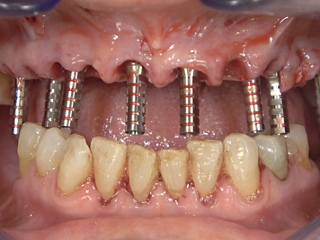

Guided FP1 maxillary rehabilitation with Straumann® STARconcept™ and Straumann iGuide™. A clinical case report by Dr. David Norré, Belgium.

Facially driven Smilecloud design with a focus on preserving tissue and bone. Planned in Smile in a Box and executed with the iGuide protocol; shared pin positions align the drill and prosthetic guides for chairside pickup of the pre-designed provisional. Day-5 follow-up shows the screw-retained provisional in place.

• Temporary Copings for SRAs placed – ready for bridge pick-up.

• Temporary bridge pre-fit check using the prosthetic guide and fixation pins.

• Day 5 post-op: screw-retained provisional in place.